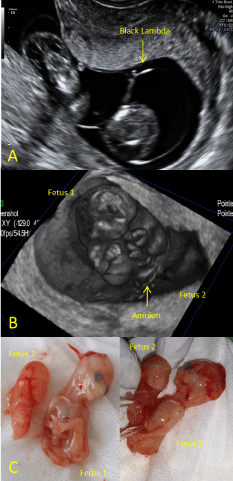

A 30-year-old primigravid woman was referred to our clinic at 12 weeks gestational age with a suspicion of an acardiac twin on a routine first trimester ultrasound scan. Expert abdominal and transvaginal two- and three-dimensional ultrasound examinations showed a monochorionic diamniotic (MCDA) omphalopagus conjoined twin (Figure 1A). Fetus 1 showed a normal intracranial anatomy, a non-covered defect of the abdominal wall with the liver out, ectopia cordis and signs of hydrops fetalis. Fetus 2 showed holoprosencephaly. The latter fetus also had a non-covered defect of the abdominal wall, absence of the heart and signs of hydrops. Only two limbs were visualized. Doppler ultrasound examination showed a single umbilical cord. Both fetuses were surrounded by a separate amniotic sac and two yolk sacs were identified. Examination with three-dimensional virtual reality confirmed these findings (Figure 1B). A provisional diagnosis of a monochorionic biamniotic conjoined twin of the heteropagus type was made.

Figure 1: Biamniotic parasitic conjoined twins A) Ultrasound examination: Two amniotic sacs surrounding the conjoined twins, with the occurrence of a 'black lambda', which indicates the pregnancy to be monochorionic diamniotic (MCDA); B) Screenshot of three-dimensional virtual reality: Showing two amniotic sacs; C) Photo of the postmortem examination of the traumatically separated twins. View Figure 1

A termination of pregnancy was performed at 13 weeks gestational age by application of misoprostol intravaginally. The fetuses showed to be traumatically separated at the time of the postmortem examination (Figure 1C). The external genitalia of fetus 1 showed to be female and the defect of the abdominal wall was confirmed, but only with the intestines extra-abdominally. Internal examination of fetus 1 showed a normal development of the internal organs compliant for the term of pregnancy, with normal localization of the heart. Fetus 2 had a proboscis, rudimentary upper limbs and a single lower limb with five digits. There was a defect of the abdominal wall. Internal organs could only be identified microscopically. Lungs, kidneys and adrenals were present. The heart could not be identified. Abdominal and pelvic internal organs could not be identified. The external genitalia were ambiguous. Both fetuses had a scoliosis with a prominent long and curved coccyx.